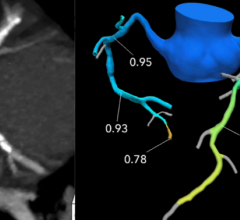

September 12, 2019 — HeartFlow Inc. has obtained clearance from the U.S. Food and Drug Administration (FDA) for the ...